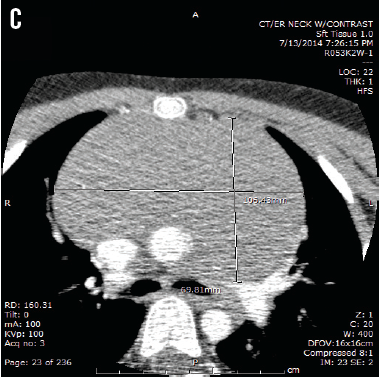

Cynthia H. Ho, MD; Randall Y. Chan, MD; Adler M. Salazar, MD; Keith E. Lewis, MD; Jeffrey L. Johnson, MD

A 7-year-old boy presented with enlarging cervical lymph nodes and progressive dyspnea for 2 weeks.